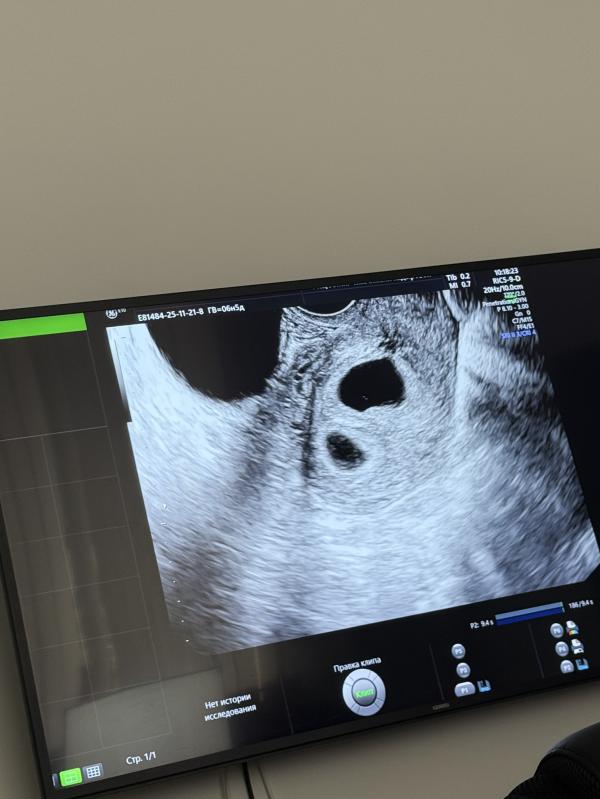

Два плодных яйца , один пустой

6,5 недель

Возможно ли что второй появится ?

Там их два, у них обычно разница в несколько дней бывает, так, что скорее двойня